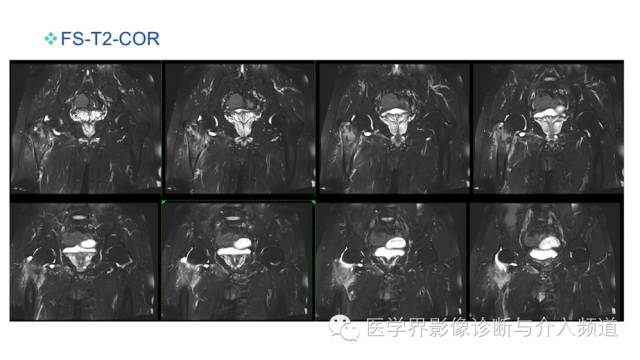

MR平扫及增强示:

右侧股骨上段见不规则形长T1短等T2异常信号,直径约1.5cm,邻近骨皮质破坏,其内骨髓可见斑片状长T1等长T2混杂信号,边界不清,股前方可见软组织肿块,呈长T1等长T2混杂信号,DWI呈明显高信号;注入GD-DTPA后,股骨内病灶呈轻度强化,周围软组织呈明显不均质强化。左侧髋关节诸组成骨对位关系可,未见明显骨质破坏征象,双侧髋关节可见少量斑片状长T2液体信号影。